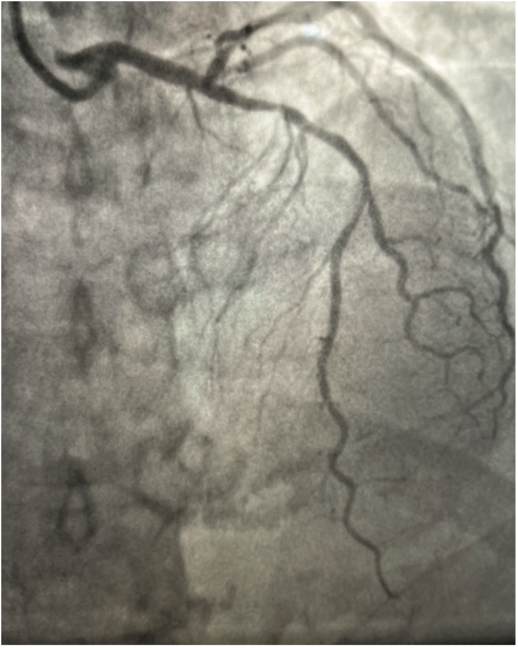

The left coronary artery was cannulated through the right radial artery with a 6 French Judkins left 3.5 guide catheter. The mid left anterior descending (LAD) artery showed a 70%-80% long lesion (Figure 1). After adequate anticoagulation with heparin, an .14-inch Runthrough wire (Terumo) was used to wire the LAD without difficulty. The patient’s vitals were within normal range. An uneventful predilatation of the mid LAD lesion with a compliant 2.5 mm x 20 mm balloon was performed. After predilatation, an angiogram showed no angiographic dissection and TIMI-III flow (Figure 2). A 2.75 mm x 38 mm drug-eluting stent was advanced to the lesion without any difficulty. The stent was positioned with a contrast puff and direct fluoroscopy. Just prior to the stent placement, the patient’s rhythm became ventricular fibrillation. The rhythm was immediately identified and a nurse began looking for defibrillator pads. Another cath lab technologist moved to the sterile drape to start cardiopulmonary resuscitation (CPR), with an adjustment of the cath lab table and fluoroscopy camera on the way. Defibrillator pads were found, and placed on the patient’s chest and side. An external shock was delivered and the patient converted to normal rhythm. Less than 30 seconds of CPR was performed. Since we were certain of the position of the stent, and no angiographically significant dissection or perforation was visualized, we deployed the stent in the mid LAD during the chaos of getting defibrillator pads and preparation for CPR. The patient remained in ventricular fibrillation even after stent deployment. Regular rhythm was restored only after an external shock and the patient immediately regained complete consciousness. Multiple coronary images were obtained, but no abnormal coronary etiology of the ventricular fibrillation could be found (Figure 3). Post dilatation of the stent was performed with a 3.0 mm noncompliant balloon. A final angiogram showed good stent apposition without any complications. A limited cardiac cath lab echocardiogram showed no evidence of pericardial effusion. The procedure was concluded successfully without any final complications.